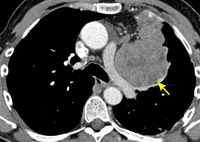

Tomografia computadorizada (TC) do tórax mostrando timoma com encarceramento e invasão da veia cava superior

Do acervo de Cameron Wright, MD; usado com permissão